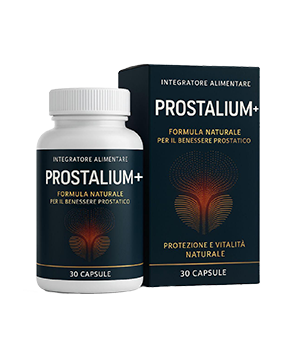

100% prodotto organico

Sicuro! -

Efficacia del 98%

dimostrata dai clienti! -

2765 uomini sono già

guariti

Rivoluzione nella cura della prostatite cronica

Efficacia dimostrata clinicamente 98% dei pazienti curati

Riconosciuto come preparato più efficace per gli uomini sopra i 40

Approvato dall’Associazione Medica Europea

Tecnologia sopra la media e 100% di componenti ecologici, senza chimicati

VANTAGGI DI Prostalium+

EVITATE I FALSI

Con l’aumento di popolarità di Prostalium+ , sono comparsi dei falsi a prezzi esilaranti. Solo qui potete acquistare il prodotto originale con lo sconto del 50%.

100% prodotto organico

Sicuro! -

Efficacia del 98%

dimostrata dai clienti! -

2765 uomini sono già

guariti

Rivoluzione nella cura della prostatite cronica